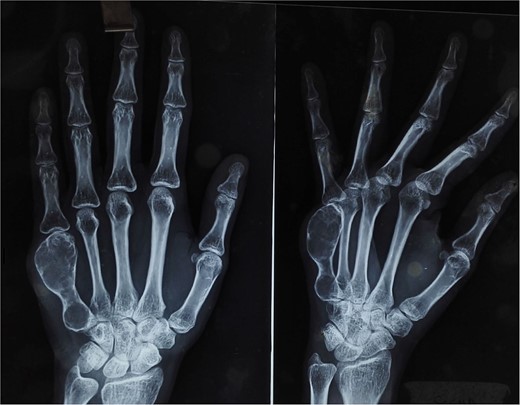

On physical examination, there was a firm, fusiform swelling over the fifth metacarpal without skin changes or tenderness. The range of motion in adjacent joints was preserved. Radiographs revealed a large, expansile lytic lesion in the diaphysis of the fifth metacarpal, with cortical thinning-indicative of recurrent GCT (Fig. 1). A biopsy confirmed the diagnosis.

X-ray of the right hand shows an expansile, lytic lesion in the diaphysis of the fifth metacarpal with a “paper-thin” cortex extending to the subchondral bone.